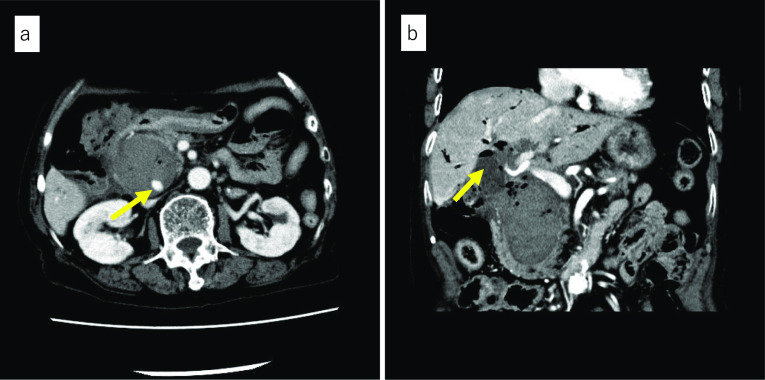

Enhanced CT at our hospital showed high-density collection, which indicated rather flesh blood and pseudoaneurysm within the cystic lesion measuring 50 mm in the pancreatic head (Fig. 1a). The gallbladder had already been resected, and the intestinal tract, which was suspected to be the lifted jejunum, was adjacent to the cystic lesion (Fig. 1b). Angiography was reperformed for diagnosis and treatment at our hospital on the day of admission, and extravasation from the pseudoaneurysm measuring 11 mm in the peribiliary vascular plexus (PBP) branched from the proper hepatic artery was recognized. The PBP was embolized as selectively as possible with n-butyl-2-cyanoacrylate (NBCA), and hemostasis was obtained (Fig. 2a, b). The clinical course after TAE was uneventful and no liver dysfunction occurred. Based on the CT findings, interventional radiology (IVR), and considerations that IDS was the standard operation for CBD in the 1950s, the cause of hemorrhage shock was determined to be due to hemobilia of the remaining dilated bile duct after IDS.